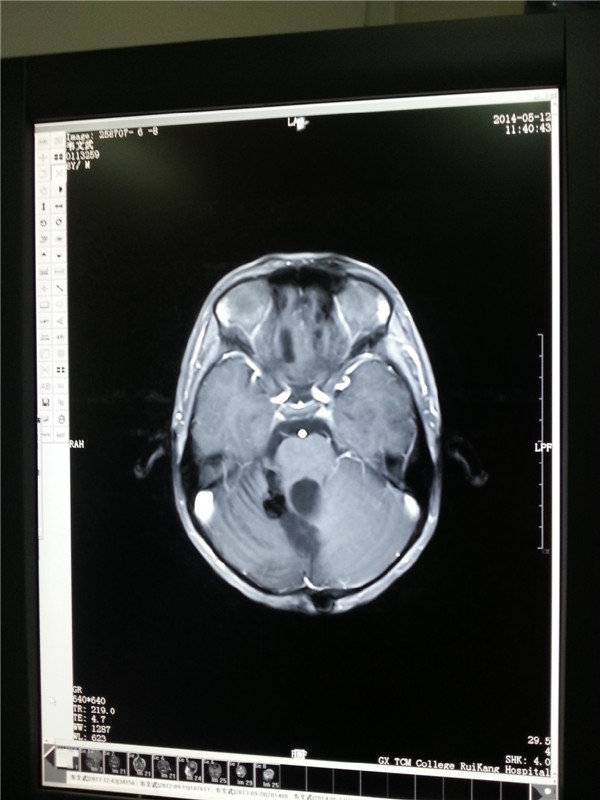

8岁的文文今年上小学二年级了,谁也想不到活泼好动的他,在三年前被检查出患有脑胶质瘤。日前,文文在父母的带领下来院复查。磁共振结果显示胶质瘤复发后采取射波刀治疗的第四年,文文的肿瘤已消失,身体状况良好。

2013.9肿瘤消失(左图);2014.5复查肿瘤无复发(右图)